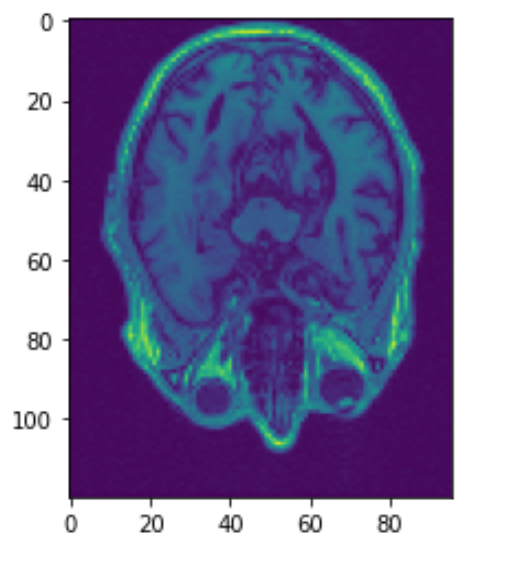

Before any analysis can be done with MRI scans, image registration must be done. Patients can be in many positions when they get their scans. The heads may be slightly tilted or rotated. Image registration normalizes the dataset so that the skulls are somewhat aligned. Below we can see the third image aligned using SimpleElastix. The 2nd image was rotated and moved slightly. The first and third image should line up well.